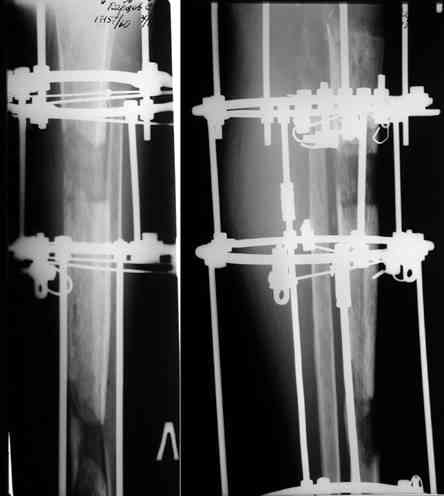

После нескольких некрэктомий, проведения аутодермопластики и заживдения ожоговой раны через 2 месяца после травмы произведен открытый остеосинтез левой бедренной кости штифтом и пластиной (деротационной) [image 01, 02]. Через 1 год и 7 месяцев после травмы у больного диагностированы ложный сустав и хронический остеомиелит левой бедренной кости. Произведено удаление металлических фиксаторов, секвестрэктомия и остеосинтез бедренной костивнешним двухплоскостным стержневым аппаратом [image 03, 04] .

Через 3 года после травмы констатировало отсутствие консолидации бедренной кости, сохранение признаков хронического остеомиелита (свищ в нижней трети левого бедра). Произведен демонтаж аппарата, реостеосинтез бедренной кости спице-стержневым аппаратом, некрсеквестрэктомия. В аппарате удалось лишь частично произвестиустранение углообразной деформации бедренной кости [image 05] .